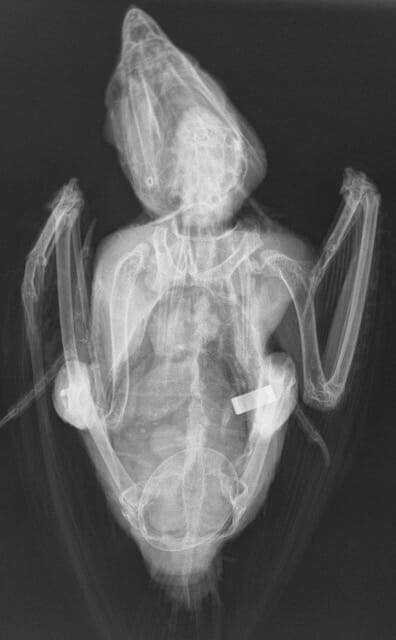

Limbs can be restrained with tape, light sandbags or ties. Ventrodorsal views are taken with the bird in dorsal recumbency, with the wings extended laterally and the legs extended caudally (Figure 2). It is not necessary for the wings to be fully extended, as long as they do not superimpose the coelomic cavity. The keel should be superimposed over the spine and the two sides of the pelvis should be symmetrical. Lateral views are taken with the patient in left or right lateral recumbency with both wings extended dorsally (Figure 3). Care must be taken when restraining the wings as too much pressure on the humeri can result in an iatrogenic fracture. The legs should be pulled ventrally and caudally to reduce superimposition on the coelomic cavity.